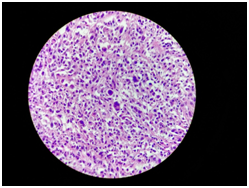

Then, induction is carried out using fentanyl, propofol and vecuronium. Maintenance with an inhaled anesthetic based on Sevoflurane, ventilatory maintenance with low flows, low tidal volume and high respiratory rate (Figure 9–10). At the end of the patient, he leaves with tracheostomy under ventilatory support to schedule withdrawal of ventilatory support (Figure 11), finish surgical procedure without complications. Capnography was normal throughout the procedure. With histopathological result anaplastic carcinoma of the thyroid (Figure 12), and subsequent reference to a center specialized in oncology.

Figure 12Anaplastic thyroid carcinoma; High grade pleomorphic tumor cells, neoplastic giant cells, spindle cells or squamoid cells in a background of tumor diathesis and inflammation.